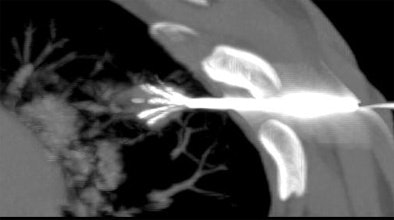

![]() |

| Above and below: Three-dimensional reconstructions of multidetector spiral CT datasets show correct placement of the radiofrequency needle into the tumor. Images courtesy of Dr. Riccardo Lencioni. |